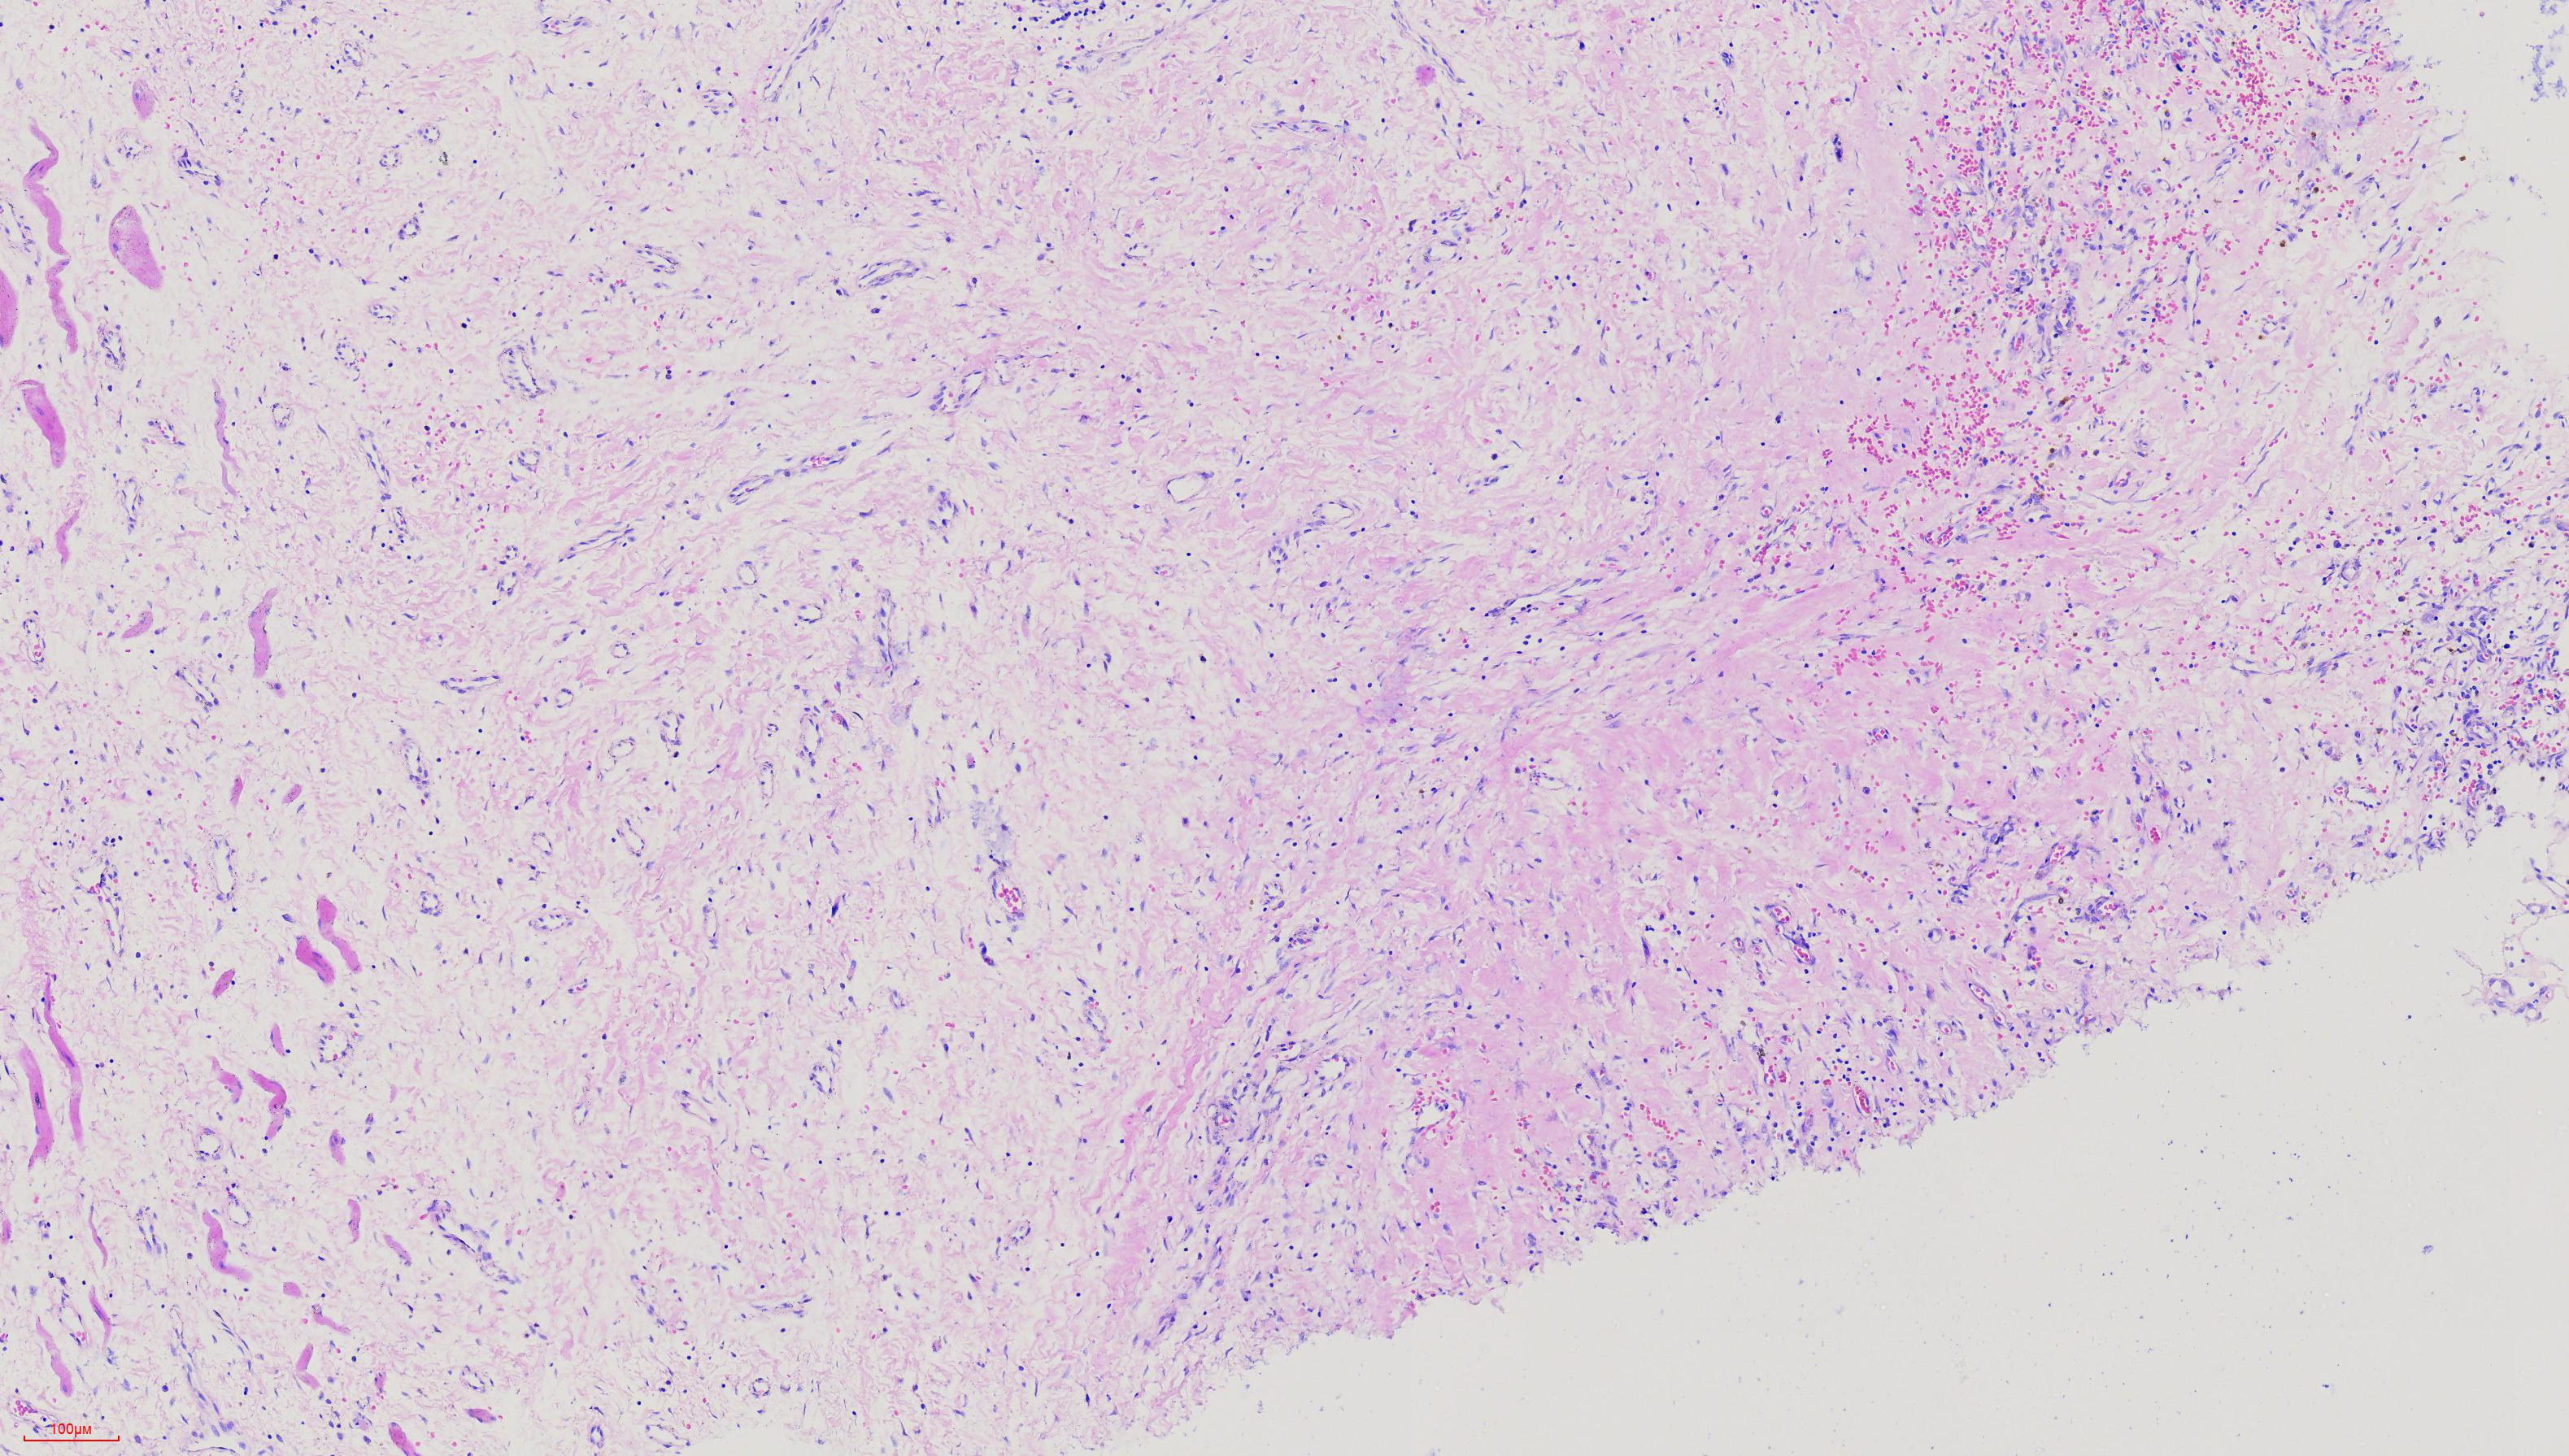

肘关节肿物

结节状组一块

图3

横纹肌、血管、纤维组织,描述诊断